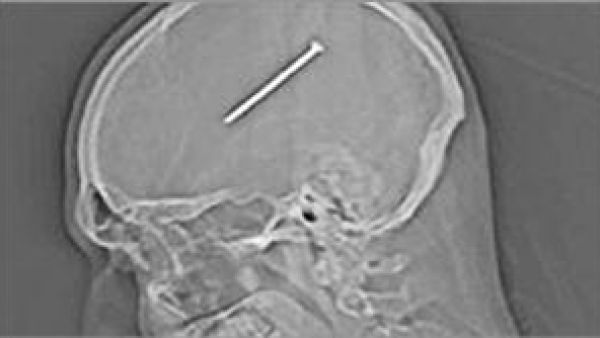

المسمار داخل الراس

تمكن جراحون من اخراج مسمار بطول 8.25 سنتيمتر من وسط دماغ شخص من ضواحي شيكاغو، ضرب نفسه عرضا به.

وقال الاطباء لدانتي «ان المسمار كان على بعد ملليمترات فقط من منطقة حساسة جدا وسط الدماغ مسؤولة عن فعاليات حيوية مهمة».